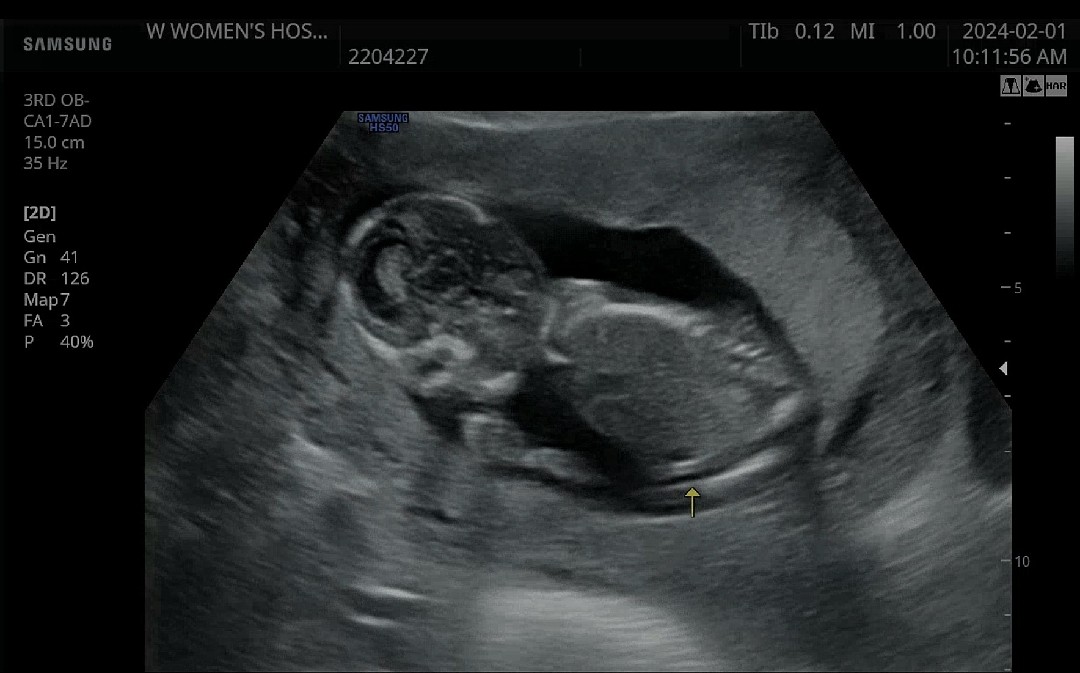

14주6일 넘나귀여워요🥹

오늘아가보고왔는데 많이크기도컸고 ㅋㅋ 손을자꾸 입에 대고 만세하고 계속움직이는데 너무 귀엽네요ㅋㅋ뭔가 벌써 통통한느낌??역시뭐눈엔뭐만보인다구..ㅋㅋㅋ모든게 귀여워보여요🤪😝 오늘 왕자님인거 같다고 힌트주셨는데 신랑이너무좋아하네요😁 20주언제기다려요...3월인데.....